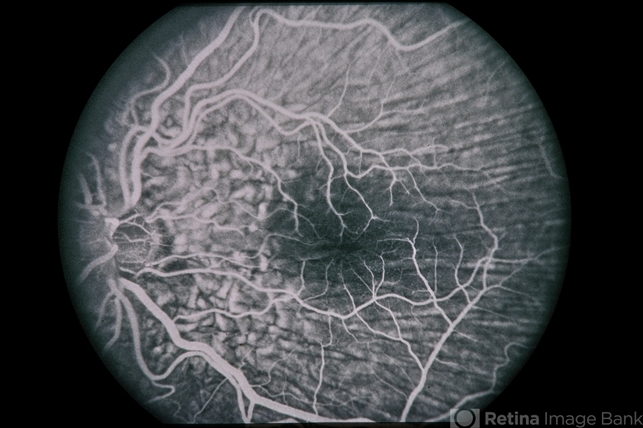

Hypotony from OverFiltration

45-year-old Hispanic male with hypotony from over-filtration.